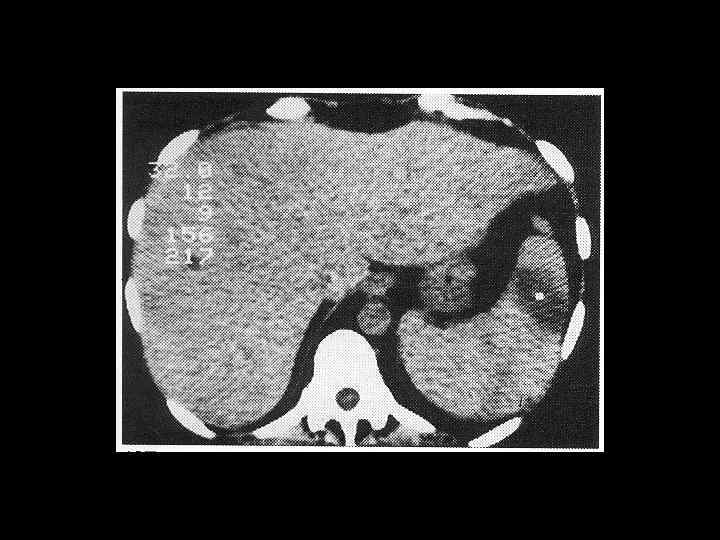

АКТУАЛЬНЫЕ ВОПРОСЫ РЕНТГЕНОЛОГИИ ЛУЧЕВАЯ ДИАГНОСТИКА ЗАБОЛЕВАНИЙ СЕЛЕЗЕНКИ Спленомегалия: Причины - Заболевания системы крови (гемолитические анемии, острые лейкозы, хронический миелоидный лейкоз, злокачественные лимфомы) - портальный цирроз печени - тромбоз селезеночной вены

АКТУАЛЬНЫЕ ВОПРОСЫ РЕНТГЕНОЛОГИИ ЛУЧЕВАЯ ДИАГНОСТИКА ЗАБОЛЕВАНИЙ СЕЛЕЗЕНКИ Кисты и абсцессы селезенки

АКТУАЛЬНЫЕ ВОПРОСЫ РЕНТГЕНОЛОГИИ ЛУЧЕВАЯ ДИАГНОСТИКА ЗАБОЛЕВАНИЙ СЕЛЕЗЕНКИ Травма и инфаркт селезенки

АКТУАЛЬНЫЕ ВОПРОСЫ РЕНТГЕНОЛОГИИ ЛУЧЕВАЯ ДИАГНОСТИКА ЗАБОЛЕВАНИЙ СЕЛЕЗЕНКИ Опухолевое поражение селезенки